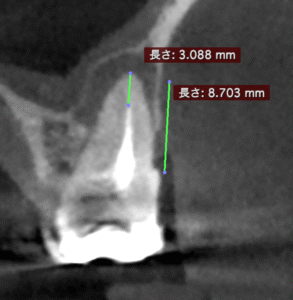

この流れで計測すると以下のようになる。

#3 MB

#3 DB

MBとDBは近接し、3mmで切断した際の頬舌的な厚みも3.5~4mmだ。

そしてMB1, MB2は近接している。

またMBもDBも近接している。

以上のことからこのApicoectomyは容易であると私にはわかる。